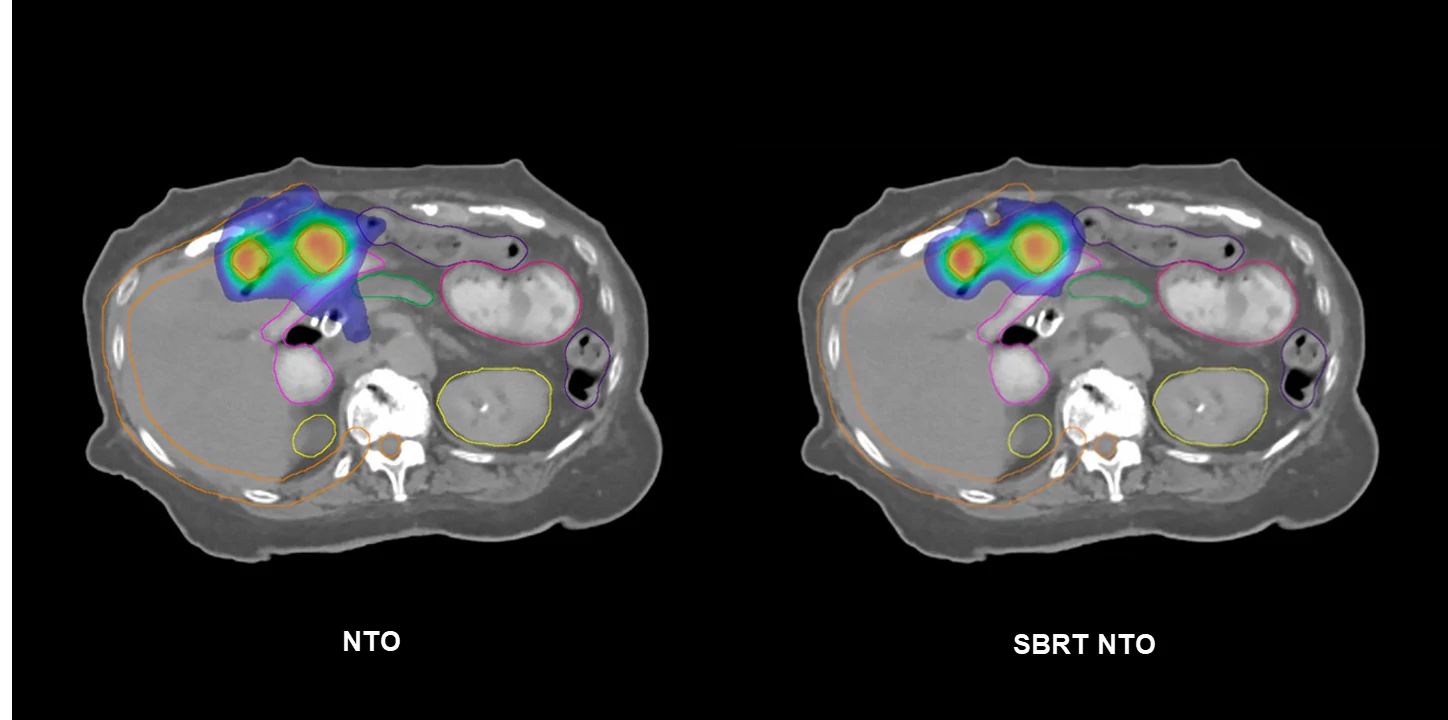

As a physicist who loves treatment planning, I would say the improvements in the Photon Optimizer (PO) have been a game changer. The Fourier Transform Dose Calculation (FTDC) advancement is one of the best things that’s happened in terms of efficiency and accuracy in the optimization process. It was eye-opening how close FTDC is to Monte Carlo and Acuros XB1 ; much closer than MRDC (multiresolution dose calculation) ever was. In addition, GPU improvements dramatically speed up optimization. PO in v18.0 also provides the ability to use SBRT NTO (Normal Tissue Objective) for the first time, which is another tool that our team has come to utilize for a variety of stereotactic cases.

SBRT NTO has reduced my reliance on rings for SBRT planning. I was accustomed to using 2-3 rings, depending on the plan, to bottle up high and intermediate dose to improve conformity. Now, I turn my SBRT NTO on and bump up the priority to match my target structures, and I observe improved conformity.

SBRT NTO has a place in the clinic for many body sites, especially as clinics are treating more oligometastatic disease. For cases where a planner is treating multiple targets in the lungs or liver, SBRT NTO aims to drive conformity and reduce dose bridging without having to add additional avoidance structures.